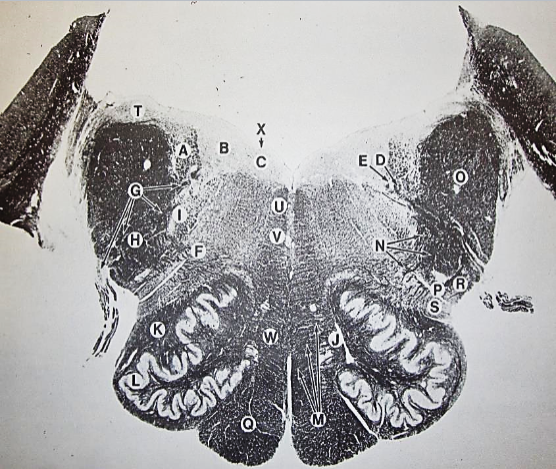

A

posterior median sulcus

B

posterior intermediate sulcus

C

anterior median fissure

D

gracile fasciculus

E

Gracile nucleus

F

fasciculus cuneatus

G

spinal trigeminal tract

H+I collectively

spinal trigeminal nucleus

J

Accessory nucleus

K

pyramidal decussation

L

lateral corticospinal tract

M

rubrospinal tract

N

posterior spinocerebellar tract

O

anterior spinocerebellar tract

P

lateral spinothalamic tract

Q

anterior spinothalamic tract

R

lateral vestibulospinal tract

S

medial longitudinal fasciculus

T

tectospinal tract

U

central canal